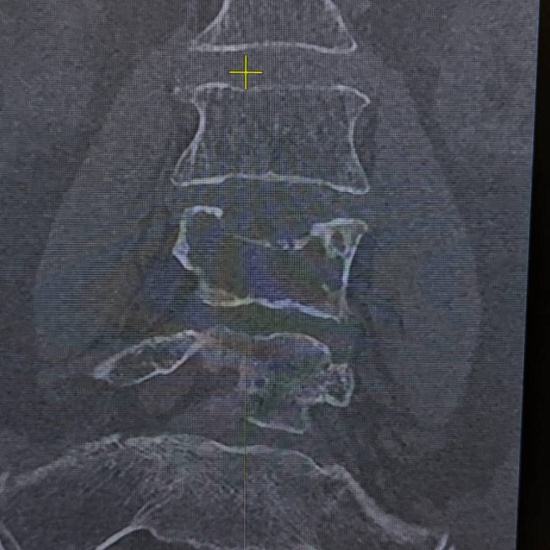

При магнитно-резонансной томографии был выявлен перелом четвертого поясничного позвонка на фоне мягкотканого образования в теле позвонка, вследствие чего пациентке было предложено выполнить дообследование в виде компьютерной томографии.

По результатам КТ и МРТ было заподозрено наличие агрессивной гемангиомы или плазмоцитомы позвонка как причины перелома.